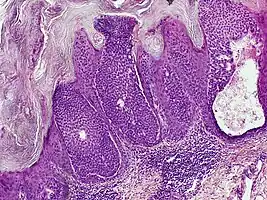

Histology

They are described as < 1 to 2 cm, pink/red shiny, exophytic lesions that can be pigmented and are clinically very similar to pyogenic granulomas.[3] Histologically, the cells as PAS-positive and clearly surrounded by normal keratinocytes. These tumors are surgically excised usually without complication or recurrence, although malignant porocarcinomas can recur and metastasize to local lymph nodes.[5]